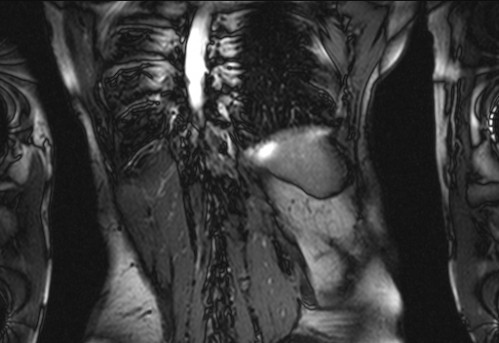

Auffälliges Abdomen bei der Vorsorgeuntersuchung einer älteren Dame

ICD: C64

68 Jahre alte Frau. Sie geht zur Darmspiegelung im Rahmen ihrer Krebsvorsorgeuntersuchung. Der Internist bemerkt bei der ergänzenden sonografischen Untersuchung des Abdomens einen auffälligen Befund.